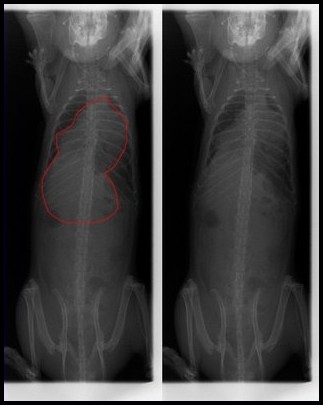

Ces photos peuvent être transmises à votre vétérinaire, afin de l'aider dans son diagnostic. Un abcès dans les poumons n'est pas toujours synonyme de corynébactéries actives, mais il convient de conserver ce détail en mémoire pour recouper les informations par la suite.

Poumons ayant des lésions typiques dues aux corynébactéries

Radio de cette rate, où on peut voir la masse